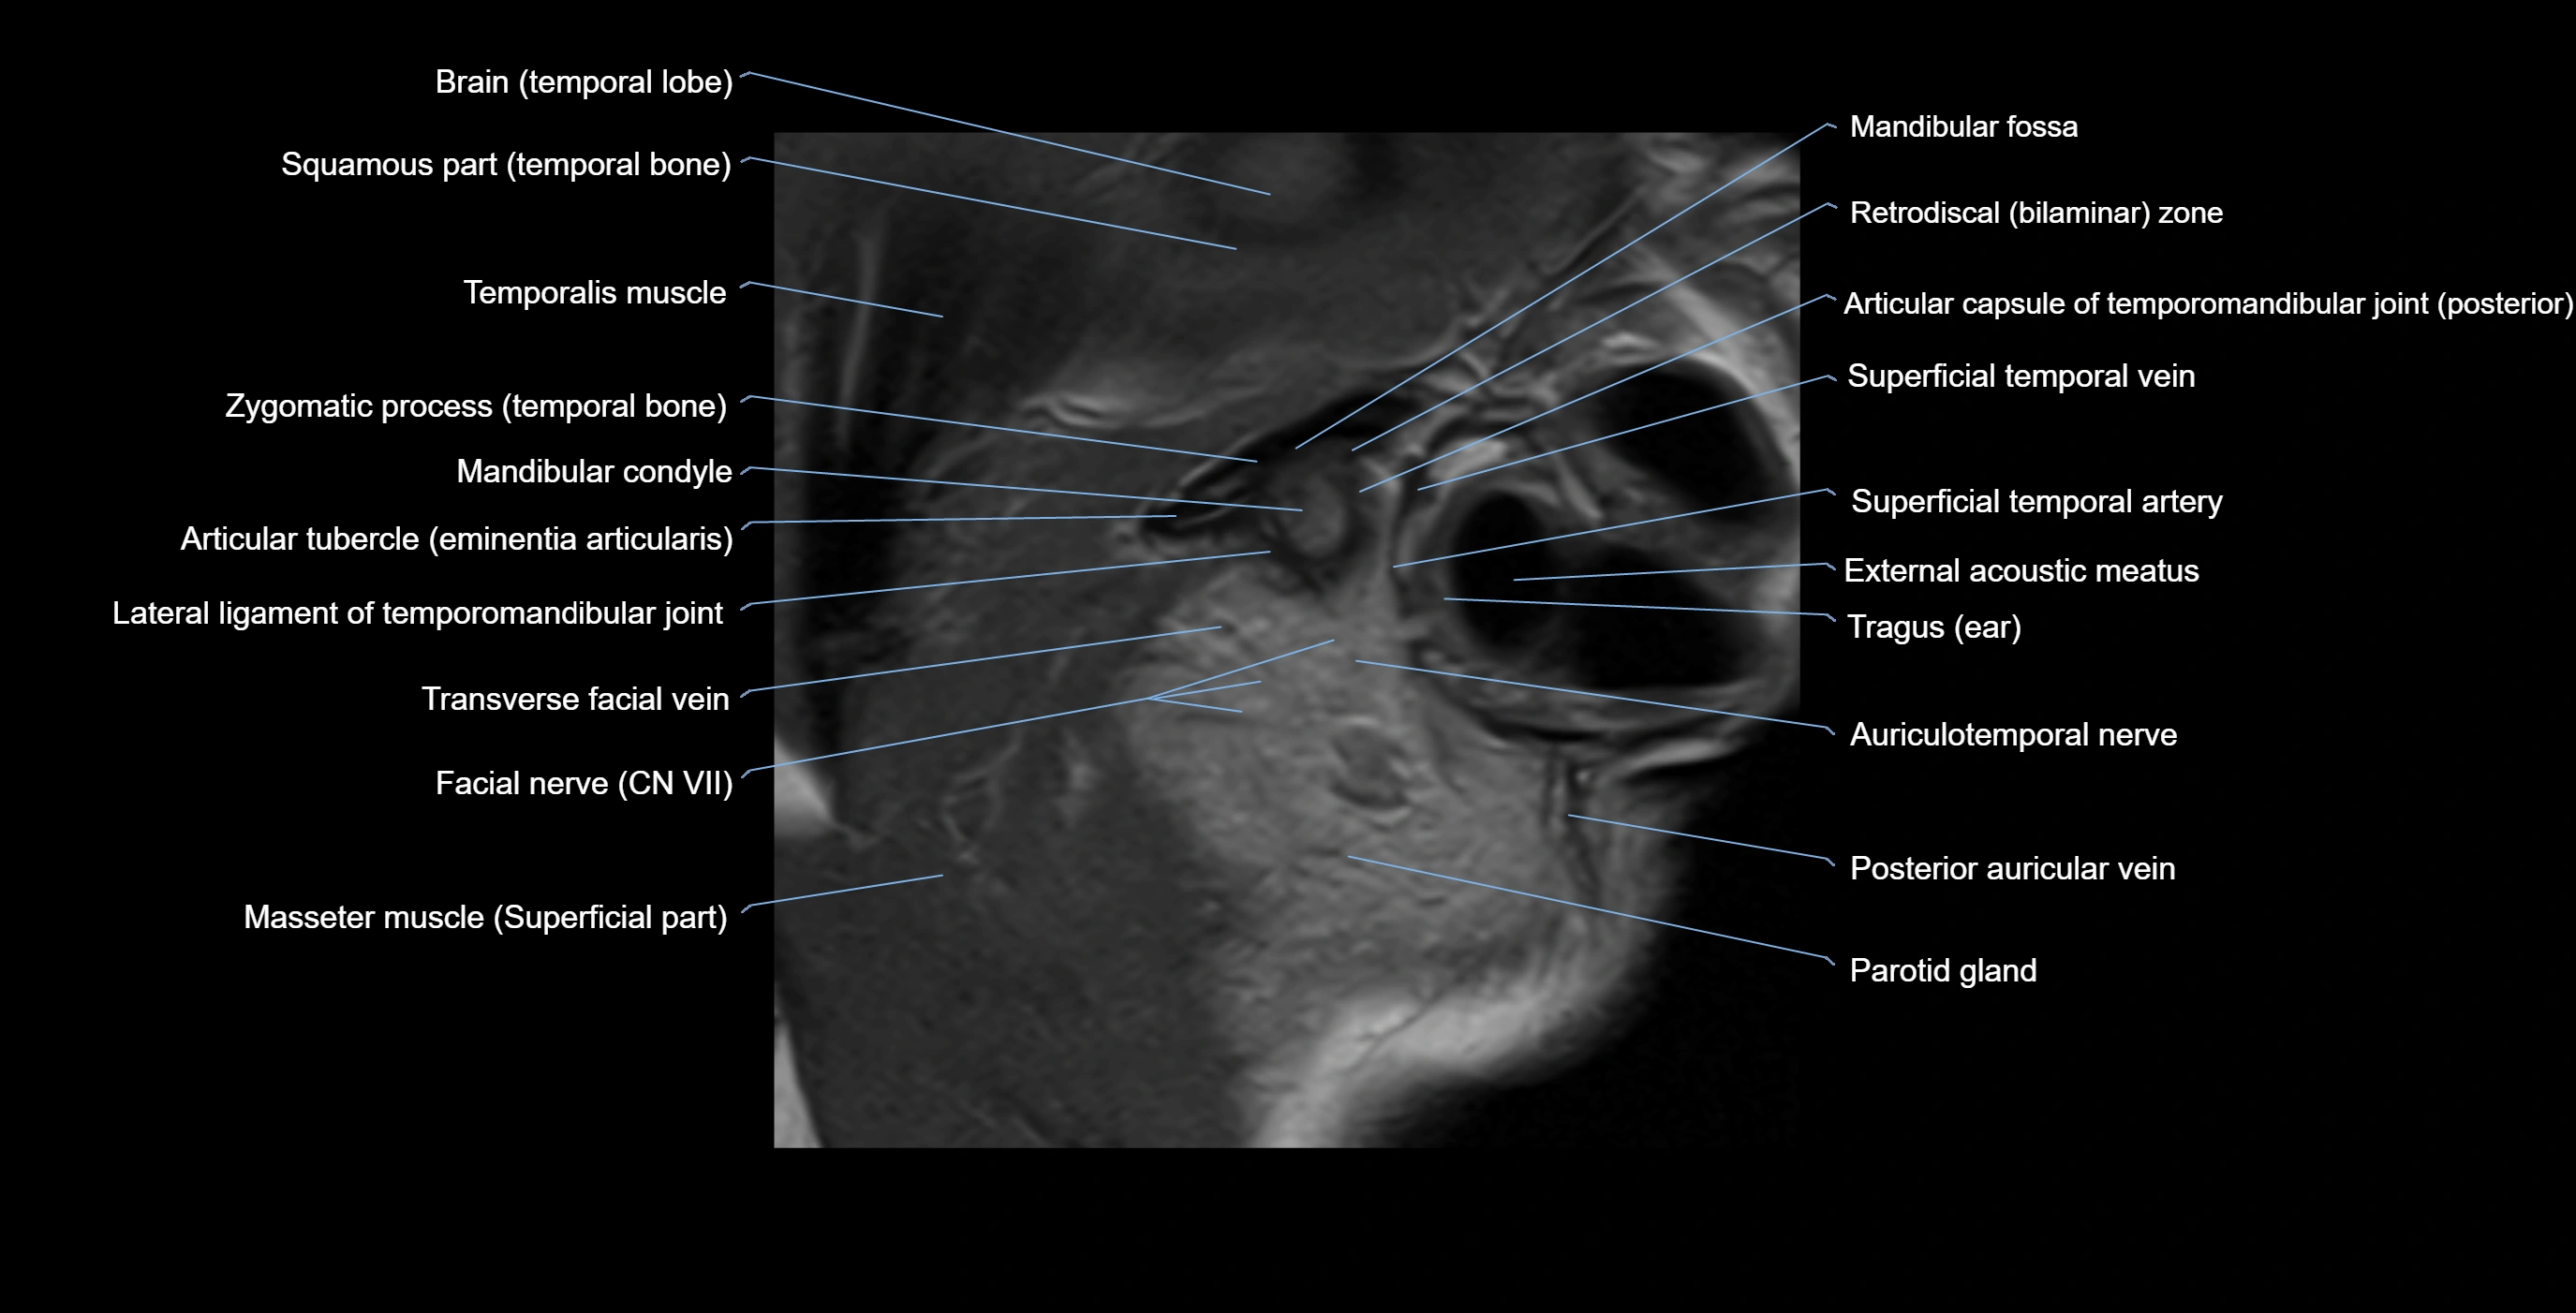

MRI appearance

T1-weighted images:

• Cortical bone: Low signal intensity

• Cancellous marrow: Intermediate to high signal depending on fatty content

• Teeth: Signal void structures

• Adjacent soft tissues: Normal gingiva and oral mucosa signal

T2-weighted images:

• Cortical bone and teeth: Low signal

• Marrow: Intermediate signal